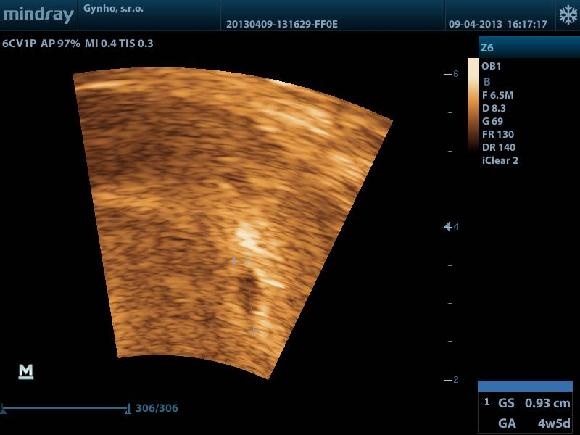

dokonce mi i doktor poslal nejake fotečky,sice nic moc nejde vidět